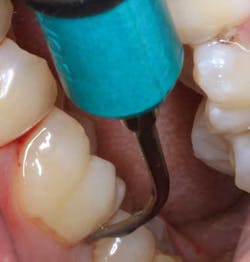

Top clinical articles

Top endodontics articles